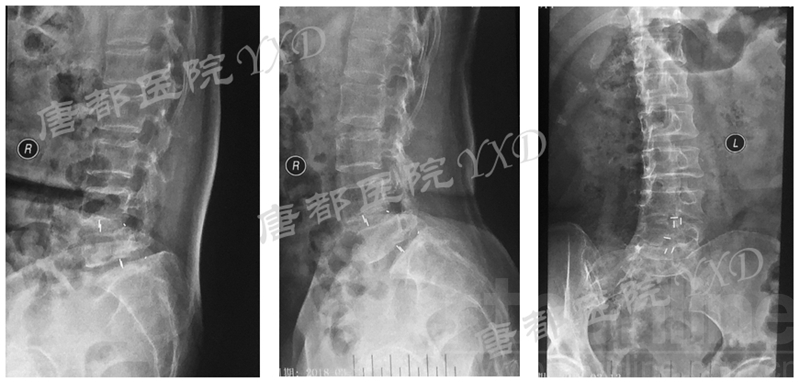

患者60岁,女性。

主诉:腰椎术后左下肢疼痛9月、加重4月。

专科情况:轮椅推入病房;强迫体位;双侧直腿抬高试验、加强试验阴性;左小腿后、外侧及足背、足底皮肤感觉减退;余未见明显异常。VAS评分:左下肢7。

既往8年前因“腰4、5椎弓峡部裂并腰4椎体滑脱症”于外院行腰4~骶1椎板减压椎间植骨融合内固定术,后因椎弓根螺钉断裂于5年前行内固定取出术。

影像学检查:

诊断:腰椎椎间融合术后融合器后移

手术方案:显微镜辅助MI-TLIF腰椎翻修术

术中视频:http://api.orthonline.com.cn/attach/Case3.mp4(术中发现因前次手术全椎板及关节突切除,TLIF的第一步,即关节突关节的定位落脚点难以找到。显微镜下通过Kambin三角解剖位置,进行从外至内的解剖,寻找cage尾端;此外,因大量瘢痕渗血,难以进行充分止血;但在显微镜的照明和放大视野下,操作均可在不伤及神经的前提下进行。由于终板骨质吸收,椎间隙塌陷,导致术野内可同时看到出行根和走行根。而在显微镜下,能够通过调整景深和视线角度,精准充分处理椎间隙骨性终板。无手术并发症)

术后疗效:VAS左下肢1分、腰1分;左侧直腿抬高试验、加强试验阴性。